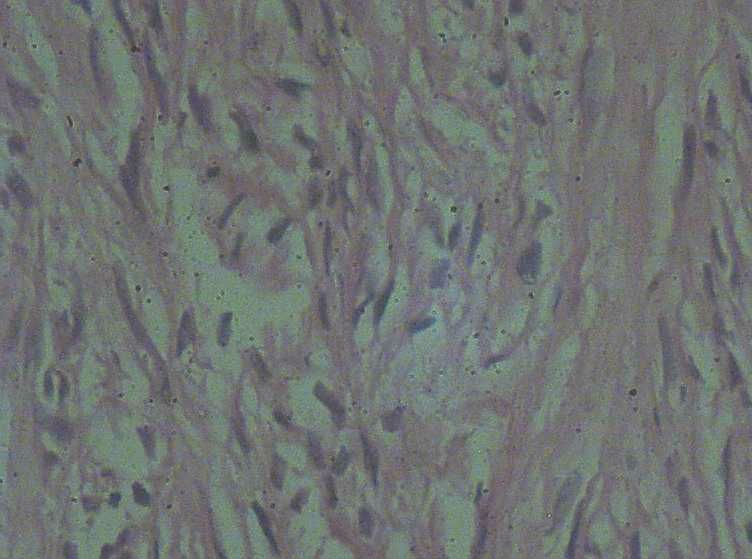

女40岁,发现乳房皮肤表面一年多。

肉眼:不整形组织1.5*1*0.5一侧见皮肤或一侧可见脂肪,切开内一小结节触之稍韧。

• 乳房皮肤表面小结节  请会诊!图2

图2

倾向于皮肤纤维瘤。

皮肤纤维瘤

良性病变。

炎症后的瘢痕结节或者纤维组织瘤样增生?